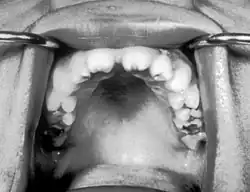

Notched incisors known as Hutchinson's teeth which are characteristic of congenital syphilis | |

Congenital syphilis that is diagnosed after 2 years of age, either because it was not diagnosed earlier or because it was incompletely treated, is classified as late congenital syphilis.[19] The signs of late congenital syphilis tend to reflect early damage to developing tissues that does not become apparent until years later,[20] such as Hutchinson's triad of Hutchinson's teeth (notched incisors), keratitis and deafness.[21][22]

- Blunted upper incisor teeth known as Hutchinson's teeth, or mulberry molars[7]

- Hutchinson's triad, a set of symptoms consisting of deafness, Hutchinson's teeth (centrally notched, widely spaced peg-shaped upper central incisors), and interstitial keratitis (IK), an inflammation of the cornea which can lead to corneal scarring and potential blindness[27]